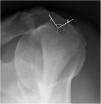

Material and MethodsA prospective study was conducted, and sixty consecutive patients proposed to shoulder arthroscopic surgery were selected. Before surgery, a radiographic evaluation was performed with a supine and a Fisk radiograph. Most supine radiographs (>75%) were non-interpretable and were excluded from the study. As some Fisk radiographs (26.7%) were also non-interpretable, that left 44 interpretable radiographs in the study. These were measured for medial opening angle, total opening angle, width and depth of the bicipital groove. The radiographic measurements and the presence of LHBT pathology, as assessed at arthroscopy, were correlated.

ResultsRadiographic evaluation of the bicipital groove showed a mean medial opening angle of 53±15o (23 – 90), a mean total opening angle of 80±26o (30 – 135), a mean width of 10.3±2.5mm (6 – 19) and a mean depth of 4.1±1.5mm (1 – 8). Men had higher medial opening angle (60 vs 50o, p=0.044) and wider grooves (11.9 vs 9.7mm, p=0.019). Twenty-five patients (56.8%) were found to have an abnormal LHBT. No correlation was found between the radiographic measurements and LHBT pathology. Only age was correlated with a LHBT lesion (61.8 vs 46.3 years, p <0.001).